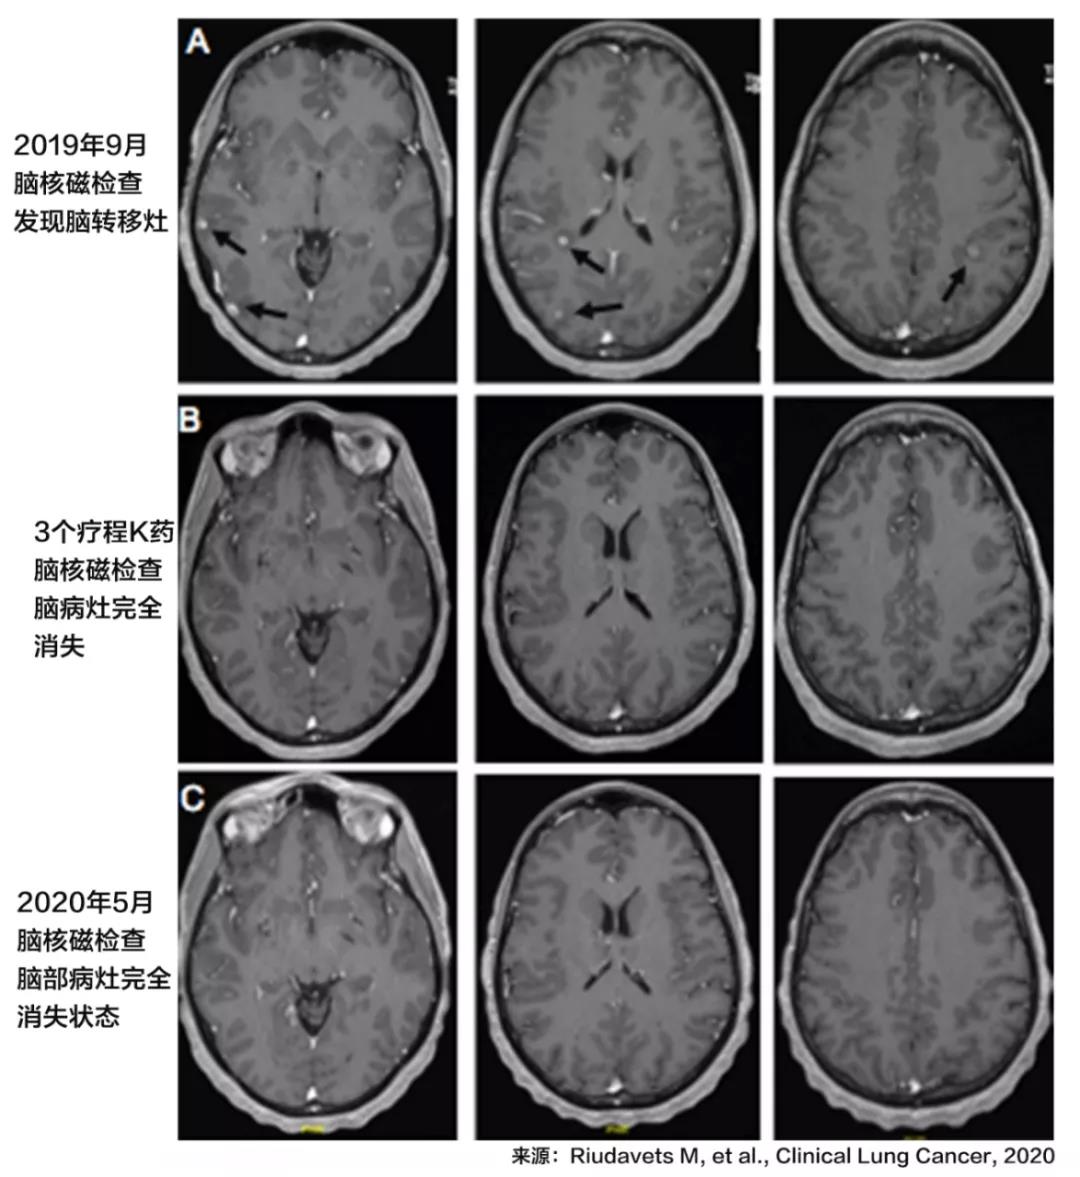

2019年9月,患者出现了新的纵膈淋巴结,肝部肿瘤复发。骨和脑都出现了转移。但是患者本身尚未出现临床症状,所以也没有进行脑放疗。治疗陷入被动局面。

在3个治疗周期之后,PET-CT扫描显示患者的多个转移病灶,包含纵膈淋巴结、骨、肝、脑的转移灶完全消失了。

2020年5月,在治疗结束后近6个月的时间里,影像学检查仍没有发现病灶,也就是达到了临床缓解。